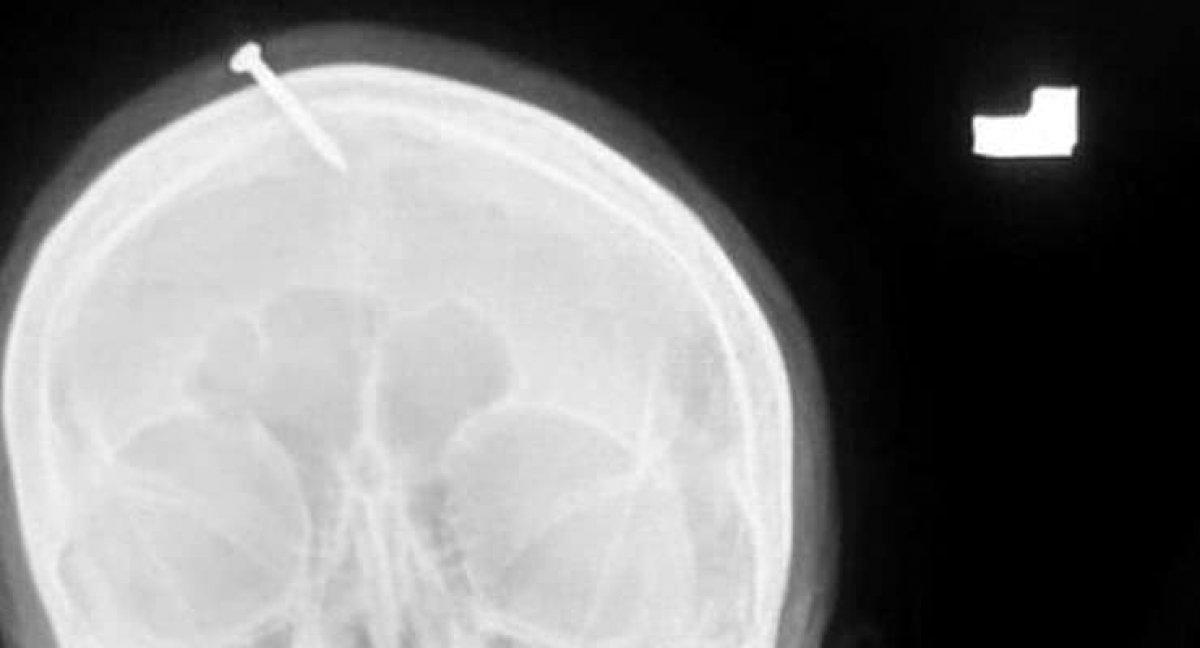

Doktor Haider Khan, hamile kadının çiviyi kafasından pense ile çıkarmaya çalıştığı ancak başaramayınca hastaneye geldiğini açıkladı. Khan, "Buraya geldiğinde bilinci tamamen açıktı ama çok acı çekiyordu. Şifacı karnındaki bebeğin kız olduğu ultrasonla kanıtlanmasına rağmen ona erkek çocuk sahibi olabileceğini söylemiş ve kafasına çivi çakmış. Çekilen röntgen çivinin kadının kafasının üzerine çakıldığı ancak şans eseri beyni ıskaladığını gösterdi." dedi.

RÖNTGEN GÖRÜNTÜLERİ ÇIKTI

Doktorlar, kadının kafasındaki çiviyi yaptıkları ameliyatla çıkardı. Çekilen röntgen görüntüleri ise sosyal medyada hızla yayıldı. Görüntüler sonrası devreye giren polis, her yer de şifacı kadını arıyor.